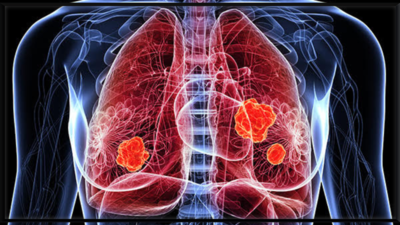

फेफड़े का कैंसर विश्व स्तर पर सबसे आक्रामक कैंसर में से एक है, आमतौर पर इसके उन्नत चरणों में निदान किया जाता है जब इसका इलाज करना कठिन हो जाता है। देरी के लिए एक प्रमुख व्याख्या यह है कि शुरुआती संकेत नरम, गैर-विशिष्ट और आसानी से मामूली बीमारी या जीवन शैली कारकों के साथ भ्रमित होते हैं। निम्नलिखित फेफड़े के कैंसर के छह शुरुआती चेतावनी संकेत हैं जो आमतौर पर व्यक्तियों को अनदेखा करते हैं-एक प्रारंभिक चरण में इसकी मान्यता एक जीवन-रक्षक अंतर बनाती है।

यदि आप सामान्य से अधिक बार सर्दी, ब्रोंकाइटिस, या निमोनिया को पकड़ते हुए प्रतीत होते हैं, खासकर यदि वे एक ही फेफड़े में आवर्ती रहते हैं या पूरी तरह से दूर नहीं जाते हैं, तो यह एक लाल झंडा हो सकता है। एक ट्यूमर वायुमार्ग को अवरुद्ध कर सकता है और फेफड़े को संक्रमण के लिए अधिक असुरक्षित बना सकता है।इनमें से कई लक्षणों को कम गंभीर परिस्थितियों से जोड़ा जा सकता है। लेकिन अगर वे हफ्तों तक जारी रहते हैं या उत्तरोत्तर बिगड़ते हैं, खासकर यदि आप धूम्रपान करने वाले हैं या फेफड़ों की समस्याओं का इतिहास है, तो डॉक्टर से परामर्श करना महत्वपूर्ण है। फेफड़ों के कैंसर का प्रारंभिक पता लगाने से जीवित रहने की संभावनाओं में काफी सुधार हो सकता है और उपचार के विकल्पों का विस्तार हो सकता है।नियमित चेक-अप, शारीरिक परिवर्तन के लिए सतर्क रहना, और धूम्रपान छोड़ना इस मूक हत्यारे के खिलाफ सबसे अच्छा बचाव है